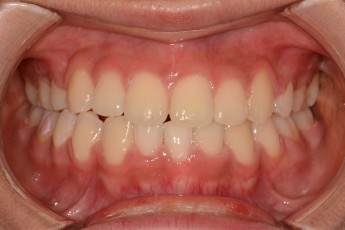

Before

After